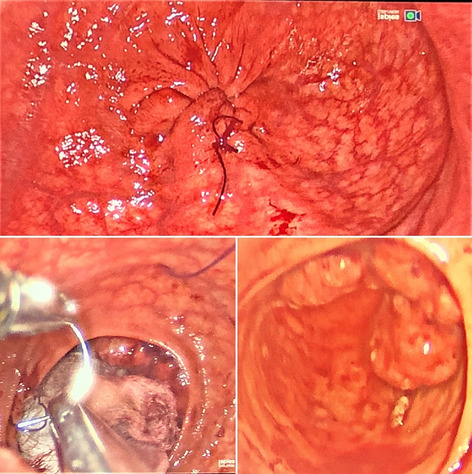

Result: The comparative analysis of the data shows a decrease in the number of presentations in ESU of AC cases during the pandemic, compared to the previous year, most often due to patients' fear of contacting the virus in the hospital environment. The median time between the onset of symptoms and the presentation in the ESU: 2020 – 14 days, 2019 – 5 days. Forms of moderate and severe AC predominated in the pandemic: GradeI—14.28%; GradeII—57.14%; GradeIII—28.57%. In 2019 GradeI—66.39%, GradeII—27.73%, GradeIII—5.88%. Laparoscopic cholecystectomy was attempted for all patients from the beginning, but the complications identified during surgery and severe forms led to a conversion rate in 2020 of 14.28%, compared to 5.88% in 2019. The severity of the cases is also observed in the postoperative complications encountered (perihepatic abscess Fig. 2. Figure 2, wound infection, bile leak; 2019—5.04%, 2020—23.21%), which required surgical reinterventions to solve them (2019: 2.52%, 2020: 10.71%). The number of deaths was significantly higher in 2020 (5.35%), compared to 2019 (0.84%).